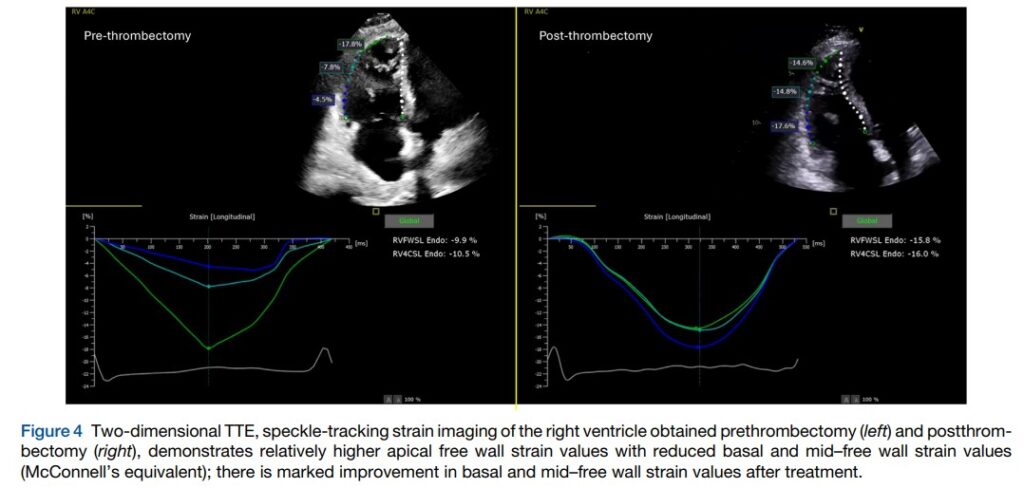

A análise do strain mostrou uma redução significativa do strain de parede livre (9.9%) e a avaliação segmentar apresentou diminuição acentuada da deformação nos segmentos basal (4.5%) e médio (7.8%) da parede livre, mas com o segmento apical apresentando um valor relativamente elevado (17.8%), sendo, portanto, consistente com o padrão de “apical sparing“.

Novo ecocardiograma, realizado após dois dias da trombectomia, mostrou melhora da função sistólica segmentar e global do VD, com aumento do strain de parede livre para 15.8%.